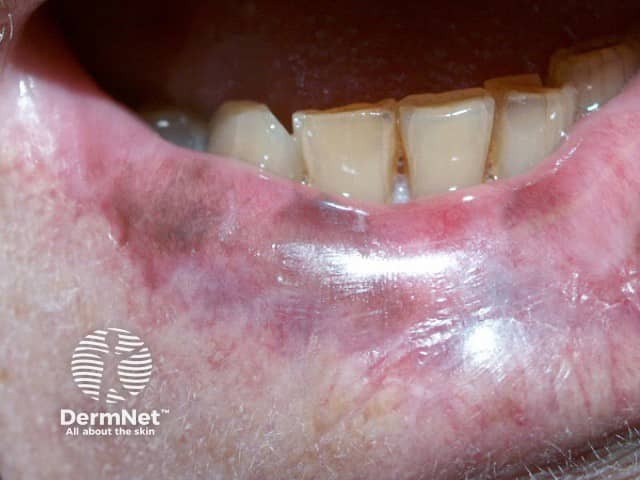

Lichen planus pigmentosus of lower lip

Pigmented contact cheilitis

The patient may present initially with burning and itchy swelling of the lip(s), suggestive of cold sores. The lip becomes progressively darker, developing a dark purple-black colour, sometimes more obvious after ceasing the product. While still using the product, the lip may be red and scaly in addition to the hyperpigmentation. However pigmented contact cheilitis is generally regarded as a non-eczematous form of cheilitis. The hyperpigmentation may be localised to just the lower lip in the case of the green tea nickel allergy, or to both lips and the vermilion border in the case of a lipstick reaction.